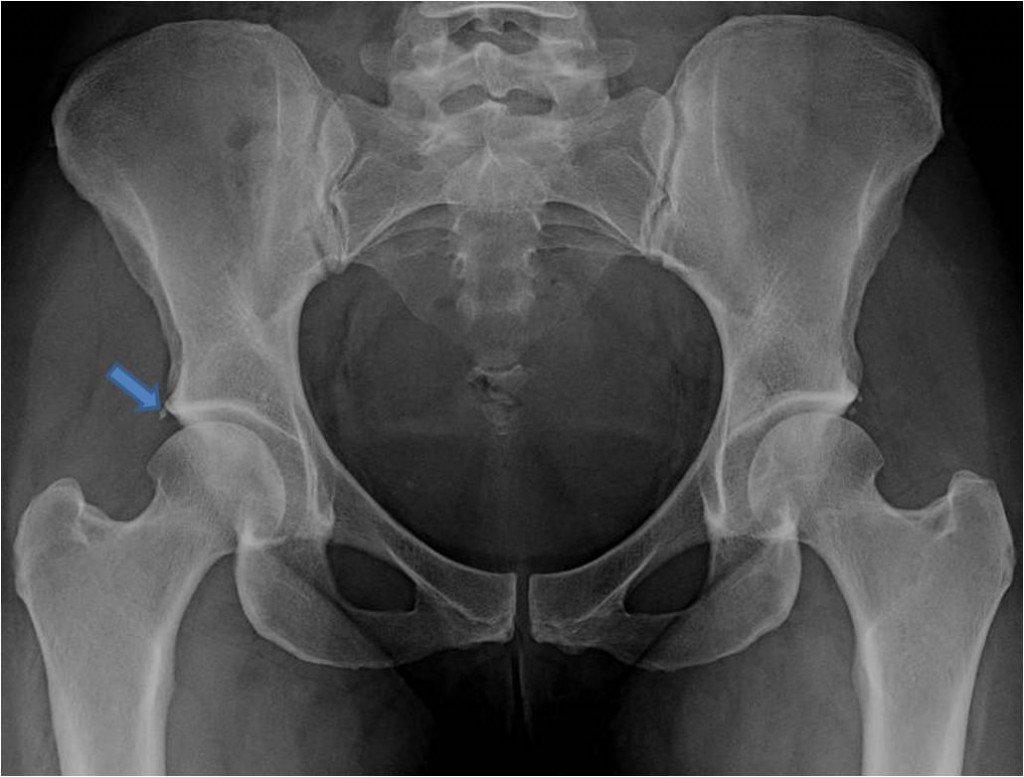

Sometimes, open hip surgery is the only way to treat large cam lesions, retroversion or hip dysplasia (something that is increasingly recognized even among arthroscopic hip. It assesses your pain, ability to complete everyday tasks like walking up the stairs, and. In a surgery for hip impingement, the surgeon will cut bone off.

Description and explanation of fai hip impingement with best conservative chiropractic treatment options. Any surgeon who does a high volume of hip arthroscopy sees patients whose hip labral tears are too degenerative or torn to sew back into place (because the labrum would not. Nwachukwu is a member of the hss hip preservation service team that brings together the expertise and experience of some of the best hip surgeons in new york city, ny and the usa.